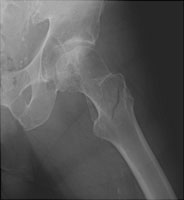

- Click on the image for a larger versionAAP radiograph of the left hip. This demonstrates an intertrochanteric fracture of the left femur.